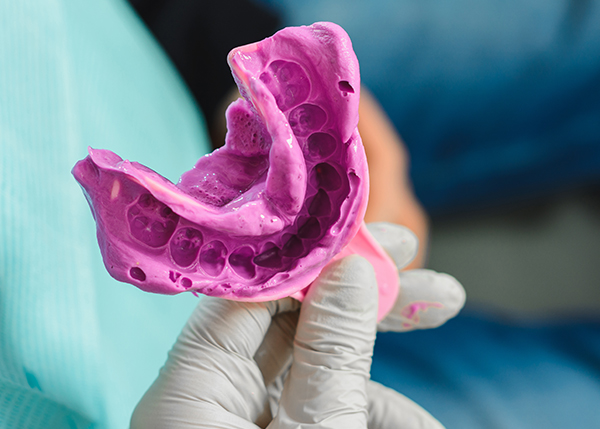

- 심미보철

CT·CAD/CAM·3D 스캔 기반의 정밀 시스템으로

치과의사와 기공사가 만드는 1:1 맞춤 보철 - READ MORE